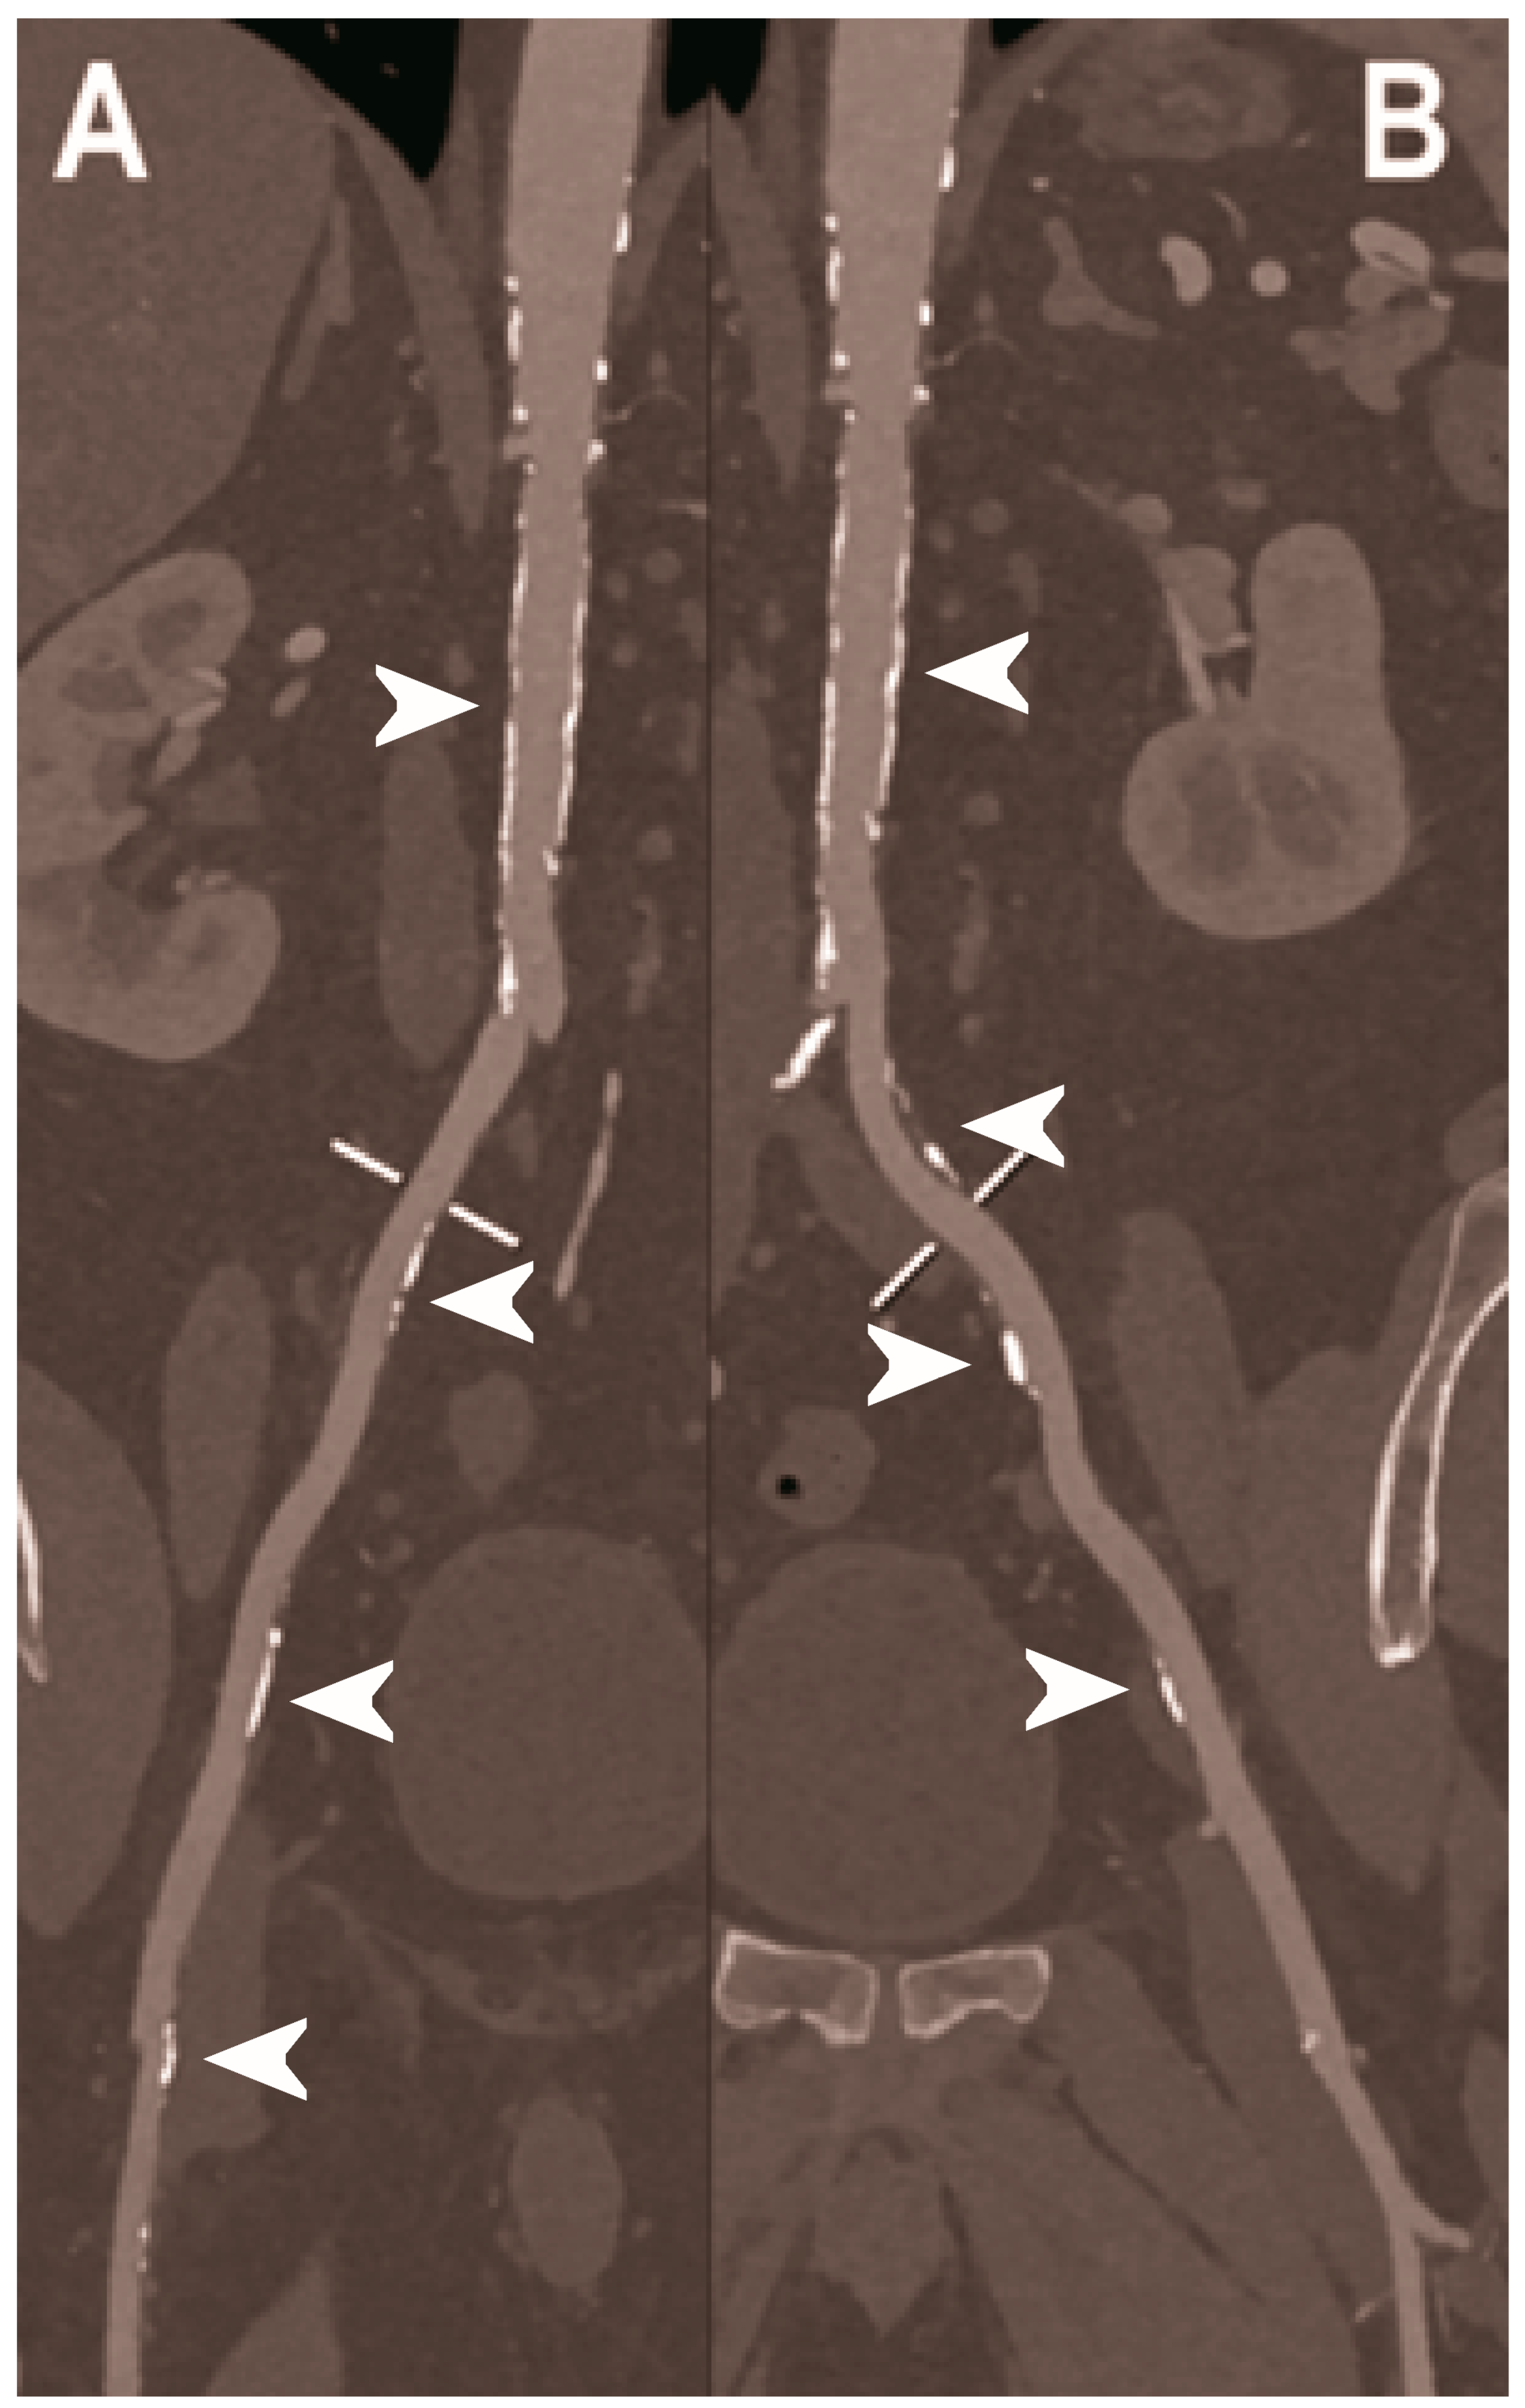

| Sigovan et al. 2019 [112] |

|